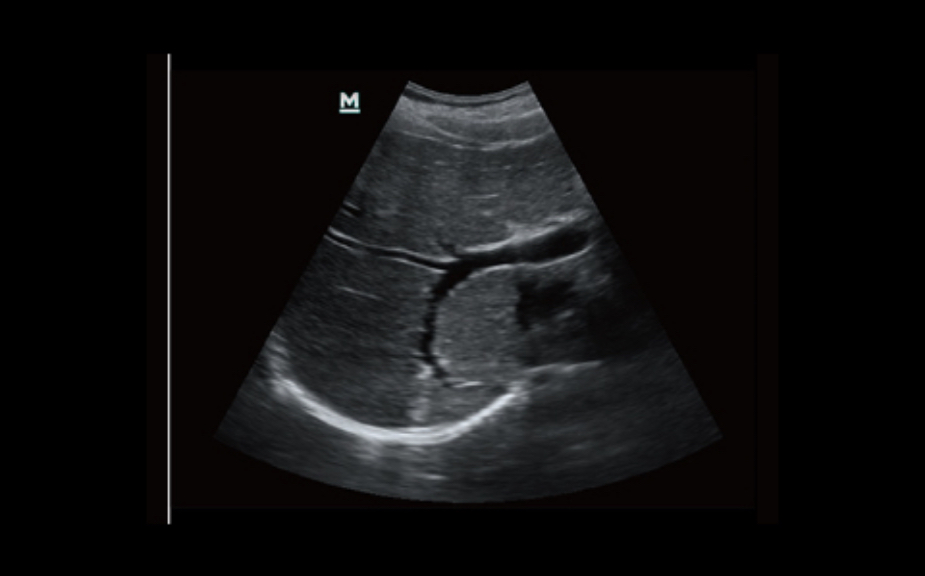

iScape?

Obtenga una vista completa y ampliada de la estructura anatĂłmica con imĂĄgenes panorĂĄmicas que, junto con la indicaciĂłn de velocidad y la capacidad de exploraciĂłn hacia adelante/atrĂĄs, hacen que la exploraciĂłn sea mucho mĂĄs fĂĄcil, mĂĄs suave y mĂĄs controlable.

ExFOV

Obtenga una mejor información de diagnóstico a través de una vista ampliada de la estructura anatómica en todas las sondas convexas y lineales.